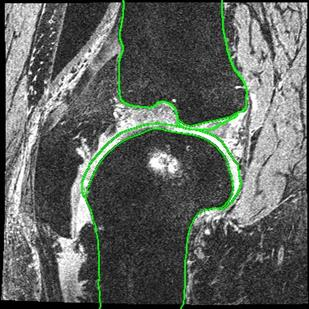

Direct automatic segmentation of objects from 3D medical imaging, such as magnetic resonance (MR) imaging, is challenging as it often involves accurately identifying a number of individual objects with complex geometries within a large volume under investigation. To address these challenges, most deep learning approaches typically enhance their learning capability by substantially increasing the complexity or the number of trainable parameters within their models. Consequently, these models generally require long inference time on standard workstations operating clinical MR systems and are restricted to high-performance computing hardware due to their large memory requirement. Further, to fit 3D dataset through these large models using limited computer memory, trade-off techniques such as patch-wise training are often used which sacrifice the fine-scale geometric information from input images which could be clinically significant for diagnostic purposes. To address these challenges, we present a compact convolutional neural network with a shallow memory footprint to efficiently reduce the number of model parameters required for state-of-art performance. This is critical for practical employment as most clinical environments only have low-end hardware with limited computing power and memory. The proposed network can maintain data integrity by directly processing large full-size 3D input volumes with no patches required and significantly reduces the computational time required for both training and inference. We also propose a novel loss function with extra shape constraint to improve the accuracy for imbalanced classes in 3D MR images.

翻译:3D医学成像的物体,如磁共振成像(MR)成像的直接自动分离,具有挑战性,因为往往需要精确地确定大量调查中大量存在复杂地理不对称的单个物体。为了应对这些挑战,大多数深层学习方法通常会大大提高其模型内可训练参数的复杂性或数量,从而提高其学习能力。因此,这些模型一般需要在运行临床MR系统的标准工作站上花很长的推断时间,并限于高性能的计算机硬件,因为它们的记忆要求很大。此外,要在这些大型模型中安装3D数据集,还要利用有限的计算机记忆,经常使用交换技术,例如补对称培训等,以牺牲从对诊断目的具有临床重要性的投入图像中获得的精细比例的几何地理信息。为了应对这些挑战,我们提出一个具有浅度记忆足迹的银色网络,以有效减少为状态性能所需的模型参数数量。这对于实际就业至关重要,因为大多数临床环境只有低端硬件,计算机功能和记忆有限。拟议的网络可以通过直接处理全尺寸三维化技术来保持数据的完整性,直接处理全尺寸的全尺寸三维的图像,从而大幅改进所需的超度变压的磁度计算。